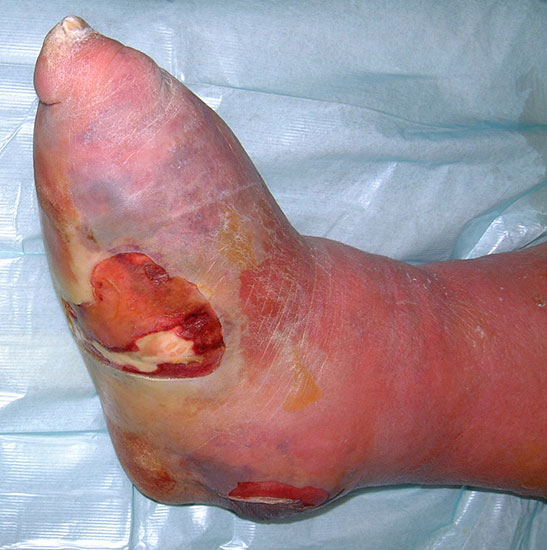

• angiopathischer Fuß:

• Ischämie von Anteilen der unteren Extremität, ohne dass eine Möglichkeit zur

• Revaskularisation besteht.

• Gewebeuntergang (Nekrose) ohne oder mit Infektion (Abb. 1)

neuropathischer / septischer Fuß:

• Eitrig einschmelzende Infektion mit septischem Zustand = Notfallindikation (Abb. 2).

• Wenn eine Gangrän oder ein Abszess zu einem septischen Zustand, [Systemic Inflammatory Response Syndrom, (SIRS) Abfall von RR, PO2, Thrombos, Anstieg von PCO2, BZ] geführt und damit zu einer lebensgefährlichen Situation geführt haben, ist die unmittelbare Operation erforderlich (Tab. 1). Eine Drainageoperation oder eine Ausräumung der Infektion kann in der Frühphase der Sepsis erwogen werden, wenn der Eiterherd lokalisiert ist und keine ausgedehnten Destruktionen eingetreten sind. Wenn durch die Entlastungsoperation keine unmittelbare Besserung des Allgemeinzustands zu erwarten ist, besteht die Indikation zur Amputation.